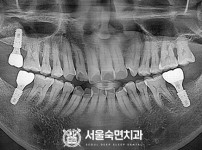

임플란트-전후사진4